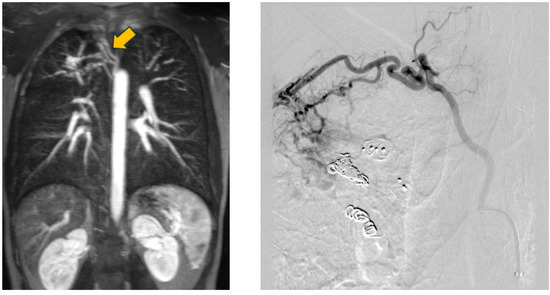

In another patient, however, the formation of collaterals between the intercostal and pulmonary arteries in the sense of aortopulmonary collaterals was detected (Figure 13 and Figure 14). Figure 15 also schematically shows the reperfusion mechanism of embolized PAVM with collateral formation.

Figure 13. MRA (left) with presentation of collateral vessels by the systemic circulation supplying the PAVM (open arrow) and confirmation by DSA (right).

Figure 14. DSA with presentation of embolized collaterals between intercostal and pulmonary arteries.